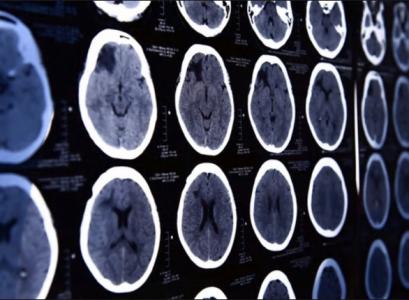

Ces dernières décennies, les techniques permettant de restaurer le flux sanguin dans les zones du cerveau compromises, touchées ou menacées par l’AVC ou encore les artères obstruées, ont connu "une explosion spectaculaire", souligne ce rapport de neurologues et de neurochirurgiens de la Loyola Medicine. Un constat à paraître dans la revue MedLink Neurology qui rend hommage aux progrès en thrombectomie mécanique et des techniques mini-invasives.

L'insuffisance vasculaire cérébrale définie comme un flux sanguin insuffisant vers le cerveau augmente le risque d'accident vasculaire cérébral et est une cause majeure de décès et d'invalidité neurologiques. Elle est généralement causée par l'athérosclérose ou l’accumulation de graisses, de cholestérol et d'autres substances qui obstruent les artères qui irriguent le cerveau.